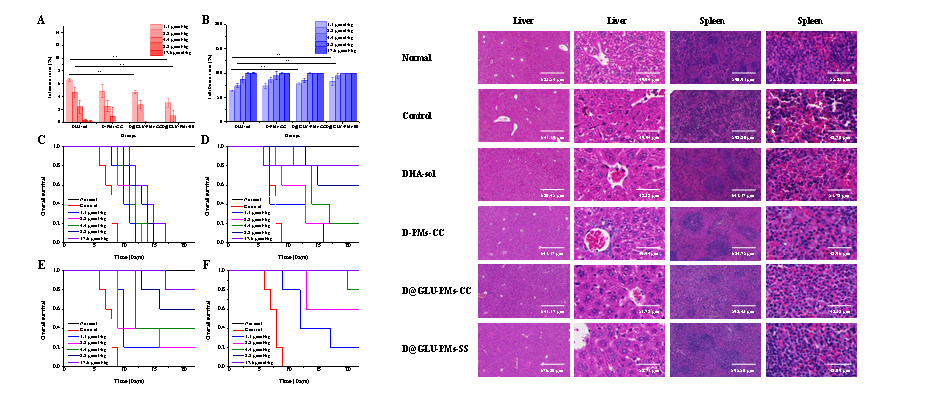

图4 DHA-sol���、D-PMs-CC��、D@GLU-PMs-CC和D@GLU-PMs-SS停药1天的感染率(A)����、抑制率(B)�����、存活情况(C����:DHA-sol����,D���:D-PMs-CC��,E��:D@GLU-PMs-CC�����,F����:D@GLU-PMs-SS)和治疗后小鼠的肝��、脾H&E染色(**P < 0.01��,n = 5)

与DHA溶液��、D-PMs-CC组或D@GLU-PMs-CC组相比��,D@GLU-PMs-SS组具有更优的抗疟活性和安全性(P<0.05)���。